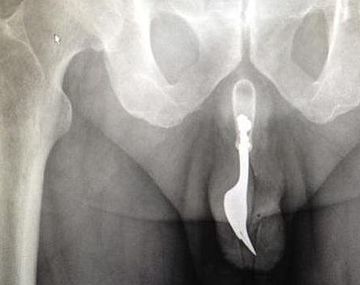

Le sacan del pene un tenedor de diez centímetros Ocurrió en Australia, cuando un hombre de 70 años intentaba disfrutar sexualmente con el utensilio de cocina y no pudo evitar que se le quedara incrustado. Rarezas